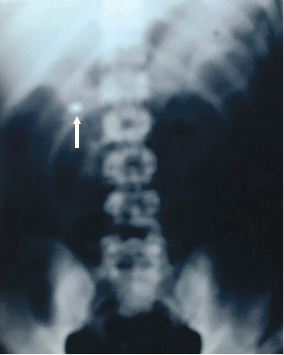

Llegó al hospital, en ambulancia y atendido por paramédicos, un individuo de sexo masculino, de 24 años de edad, con una herida de bala en el hemitórax izquierdo, sin orificio de salida. El paciente se encontraba razonablemente estabilizado, con dos venas canalizadas y oxígeno. Estaba consciente y declaró que su vecino le disparó como a tres metros de distancia por una discusión. Las vías respiratorias estaban permeables, la TA 82/44, con 124 latidos cardiacos por minuto. Las radiografías de tórax localizaron el proyectil en el espesor de la pared del ventrículo izquierdo (Figura 1). El orificio de entrada era nítido y se ubicaba ligeramente arriba de la tetilla izquierda, a cinco centímetros del borde izquierdo del esternón. El sangrado externo no era profuso. Bajo anestesia general, se realizó toracotomía anterolateral a la altura del quinto espacio intercostal. Se aspiraron 80 mL de sangre de la cavidad pleural. En el lóbulo superior izquierdo del pulmón se identificó la herida, que prácticamente no sangraba y dejaba escapar muy poco aire. El pericardio se encontraba perforado por el proyectil. Existía hemopericardio, pero sin llegar a tamponade, seguramente debido a que el proyectil incrustado en el espesor del ventrículo lo impedía. Se procedió enseguida a abrir el pericardio en toda su longitud, separando los bordes con suturas a tracción con objeto de tener un campo visual operatorio adecuado. La herida de la bala se localizó en la parte alta del ventrículo izquierdo, muy cerca de la arteria coronaria descendente anterior. No era nítida e iba a ser difícil repararla. El proyectil no se visualizó. Tratamos de localizarlo en el espesor del músculo, pero sin lograrlo. Con cada latido del corazón, escapaba escasa cantidad de sangre por la herida. No intentamos emplear una pinza de Allis por temor de ampliar la herida o lesionar la coronaria. En vista de la situación, decidimos explorar el interior del ventrículo a través de la orejuela. La aurícula, válvula mitral y estructuras subvalvulares se encontraron completamente normales, pero la bala no se halló. Solicitamos la presencia de los técnicos en imagenología en el quirófano para tratar de ubicar el proyectil por medio de radiografías. En el tórax, los resultados fueron negativos, pero en la placa de abdomen se visualizó el proyectil a escasa distancia del riñón derecho. Se procedió de inmediato a suturar cuidadosamente la herida cardiaca con Prolene 2-00 con tres puntos en “colchonero” verticales anclados con teflón, tratando de no involucrar a arterias coronarias y cerciorándonos de que no sangraba. La toracotomía se cerró, dejando dos sondas de drenaje sin succión. Acto seguido, se reposicionó al sujeto para realizar la intervención adecuada, con objeto de recuperar la bala. El proyectil, calibre 22, se encontraba en el interior de la arteria renal derecha antes de su división (Figura 2). Se procedió a retirarlo, reparando enseguida el vaso. El herido evolucionó satisfactoriamente. Fue externado a los siete días. Se revisó a las dos semanas y se le observó muy bien.

Figura 1: El proyectil se encontraba alojado en el espesor de la parte alta del ventrículo izquierdo.